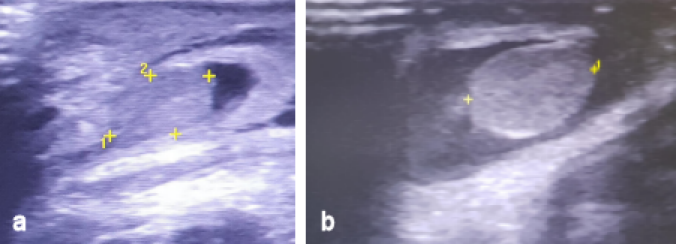

At the 4th day of life, the phototherapy was stopped. Due to the progressing clinical condition at the groins and scrotum, we conducted a new ultrasonography at these areas. The scrotal wall was grossly thickened and edematous, while the echogenic structure and vascularity of both testicles were normal (Figure 2a, b [Fig. 2]). Based on the clinical image, the finding concerned a hematoma of the scrotum. In this phase, no hydrocele was observed.

Figure 2: a) Ultrasonography of the right testicle. b) Ultrasonography of the left testicle. Both testicles are depicted inside the scrotum. The scrotal wall as well as the testicles are grossly thickened and edematous, while the echogenic structure and vascularity of the testicles are normal.